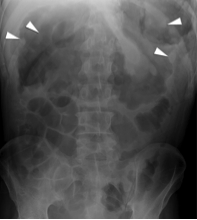

What is an obstruction?

What is the normal bowel diameter?

What type of imaging would you use and not use? (what are some features to each)?

What do you see upstream of the obstruction? downstream?

Blockage of flow of fluid or air within a lumen channel (can happen anywhere in the GI, biliary system, pancreatic duct, etc); numerous etiologies (strictures, adhesions, stones)

Normal small bowel diameter: < 2.5cm transverse diameter

Upstream of obstruction - lumen dilates; usually presence of air-fluid levels (may show up as a string of pearls sign (air trapped in plica circularis))

Downstream of obstruction – lumen decompresses as normal flow of fluid/air evacuates the lumen distal to the obstruction